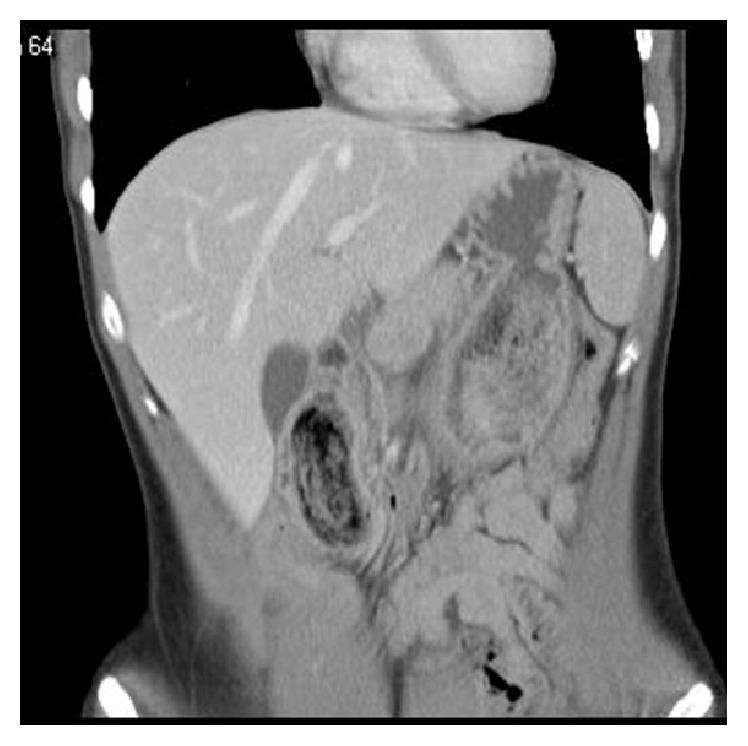

A 17-year-old girl presented with bilious vomiting and abdominal pain to the surgery department. The history was positive for trichotillomania and trichophagia. A CT scan showed a mass in the stomach, which was highly suspicious for a gastric bezoar. Drooping parts of the bezoar caused a duodenal obstruction with secondary acute pancreatitis. The bezoar was removed via a laparoscopically performed gastrotomy.

一名17岁女孩因胆汁性呕吐和腹痛就诊于外科。病史显示有拔毛癖和食毛症。CT扫描显示胃内有一肿块,高度怀疑为胃石。胃石下垂部分导致十二指肠梗阻并继发急性胰腺炎。通过腹腔镜胃切开术取出了胃石。